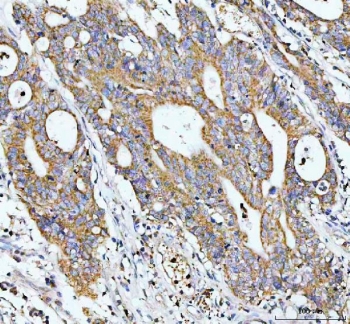

IHC staining of FFPE human colorectal cancer tissue with GCLC antibody. HIER: boil tissue sections in pH8 EDTA for 20 min and allow to cool before testing.